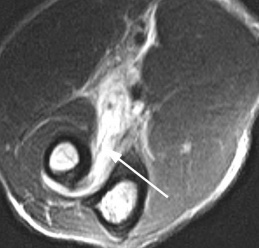

(Справа) На сагиттальной МРТ PDBИ определяется частичный отрыв сухожилия трехглавой мышцы с небольшим оторвавшимся костным отломком МРТ может быть информативна при оценке степени повреждения трехглавой мышцы. (Слева) На сагиттальной КТ с реформатированием можно видеть раздробление локтевого отростка после падения на локтевой сустав. Перелом открывается на суставную поверхность в нескольких местах.

• Линия перелома лучше видна на сагиттальной и фронтальной Т1ВИ и Т2ВИ FS

о МРТ для оценки целостности трехглавой мышцы

о МРТ: сагиттальная и осевая Т2ВИ для оценки перелома и целостности трехглавой мышцы

На МРТ локтевого сустава при любом переломе видна реакция костного мозга. Это помогает в диагностике, если перелом сразу не виден на рентгенограмме. В дальнейшем можно прицельно дообследовать подозрительную область. При консолидировавшихся переломах на МРТ остается видна линия перелома, а окружающий костный мозг нередко подвергается жировой дегенерации. МРТ в СПб стало необходимым компонентом обследования пациентов с травмой суставов и осуществимо в высоких полях или открытом МРТ. МРТ СПб дает возможность исследовать методом МРТ локтевой сустав в разных центрах, однако, наш опыт позволяет рекомендовать обследование именно у нас.

Рентгенограмма (слева) и МРТ локтевого сустава (справа). Суставная мышь (стрелка). Выпот и синовит на Т2-взвешенной МРТ.